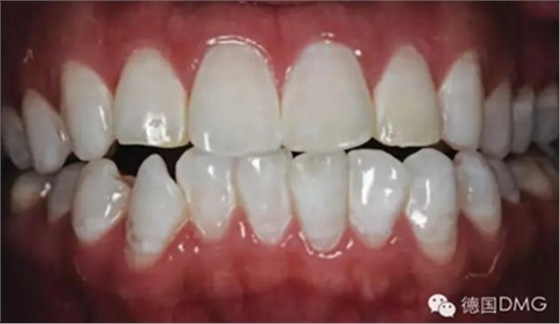

經(jīng)拋光, 治療結(jié)果令人滿意并且印象深刻 (Fig. 7 and 8)。